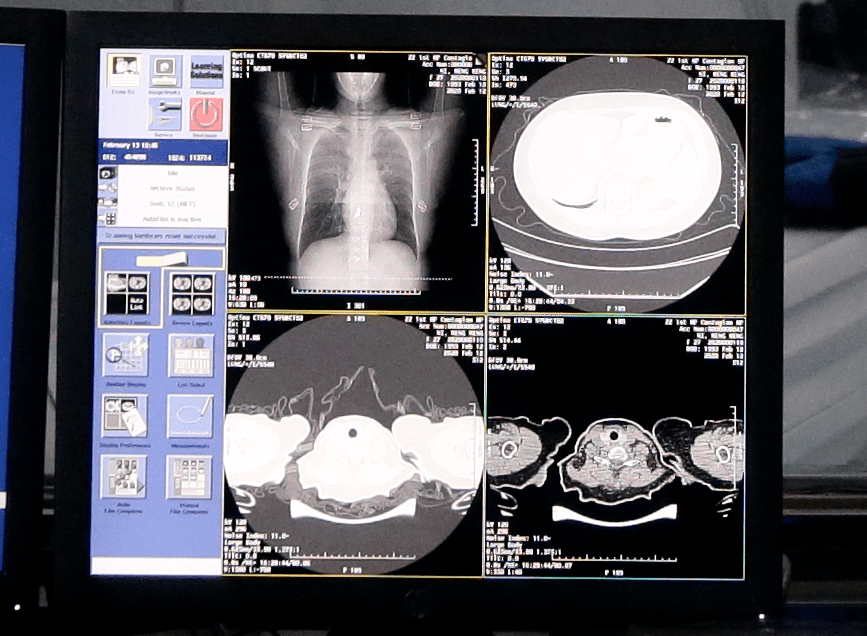

所以今天我们主要就一个相对常见的应用场景(AI技术和肺部影像结合:CT室医生看片时,AI如何帮助医生更快、更准确的判断肺部病情)、一个正在进行的建设场景(在大城市和乡村地区建设“AI+智慧医疗”会有什么不同)浅浅展开。

一位智慧医疗领域专家告诉我们,传统诊疗流程中,医学影像阅片需要耗费大量时间和人力,而人工智能技术可以快速且准确地分析医学影像,完成病灶识别、筛查、分割等工作,帮助医生快速做出诊断和评估。

以肺结节CT筛查为例,人工智能技术可以帮助医生提高微小结节检出能力,实现毫米级肺结节病灶自动检出,同时自动计算长短径、面积、体积等量化指标。对于实性、磨玻璃、混合、钙化等不同类型结节均能高效检出,提高阅片效率2倍以上,可有效助力肺癌早筛。

此外,传统影像诊断流程中,医生需要基于二维的医疗影像进行诊断,如需更直观的观察,需要借助后处理站进行器官三维重建,耗时较久,成本也较高。在人工智能技术的帮助下,能在短时间内快速完成病灶、血管、组织器官的三维重建,清晰展现病灶和邻近脉管、器官的相对位置关系。

国内,肺炎患者的阶段性暴涨也一度让不同科室的医护人员聚集到呼吸科。人工智能影像辅助诊断方法帮助医生们提升了阅片时的工作效率——中国科学技术馆相关数据,AI智能影像识别进入新冠肺炎病毒医学影像筛查后,病例CT影像数据识别时间被压缩到20秒以内,最终识别准确率达90%以上。

肺炎患者从入院到出院一般需要拍摄四次左右的CT影像,在传统的CT影像量化评估过程中,每拍摄一次CT,医护人员都需要手动勾画三四百张的CT影像,通过肺叶计数或肺段计数来统计肺叶、肺段的病变范围,从而评估新冠肺炎的严重程度,这一过程耗时长达五六个小时。但当AI遇上疑似病例,会自动发起对可疑区域的重点识别,自动统计各个肺部解剖结构中肺炎区域的占比,形成量化数据提供医生,缩短评估和阅片时长。

得益于医疗模型的云端存储,患者的过往病历及拍摄的CT影像可被调取并对重点病灶区域进行对比呈现,让医生提升对患者病情的把握程度。